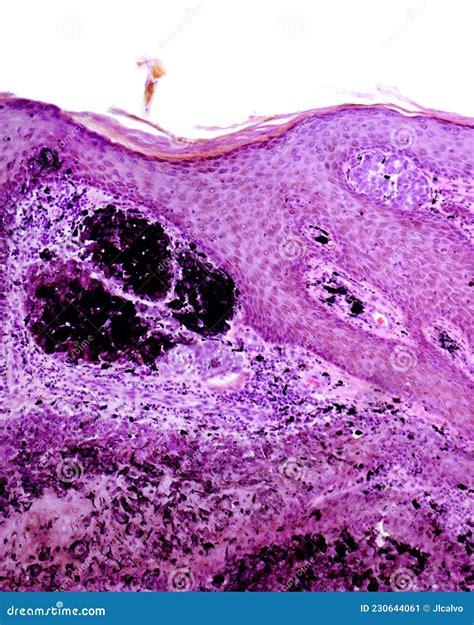

An Intradermal Pigmented Nevus is a type of mole that develops within the dermis, the layer of skin beneath the epidermis. Unlike other types of moles, which can be raised or flat, intradermal nevi are typically raised and have a smooth, dome-shaped appearance. They are often flesh-colored or slightly darker and can appear anywhere on the body. These nevi are usually present at birth or develop during childhood and adolescence.

• Dermoscopy: This non-invasive technique uses a specialized microscope to examine the mole more closely. It can help differentiate between benign and malignant lesions.

• Biopsy: In some cases, a biopsy may be performed to confirm the diagnosis. This involves removing a small sample of the mole for laboratory analysis.

• Color Changes: Changes in color, such as darkening or the appearance of new colors within the mole.